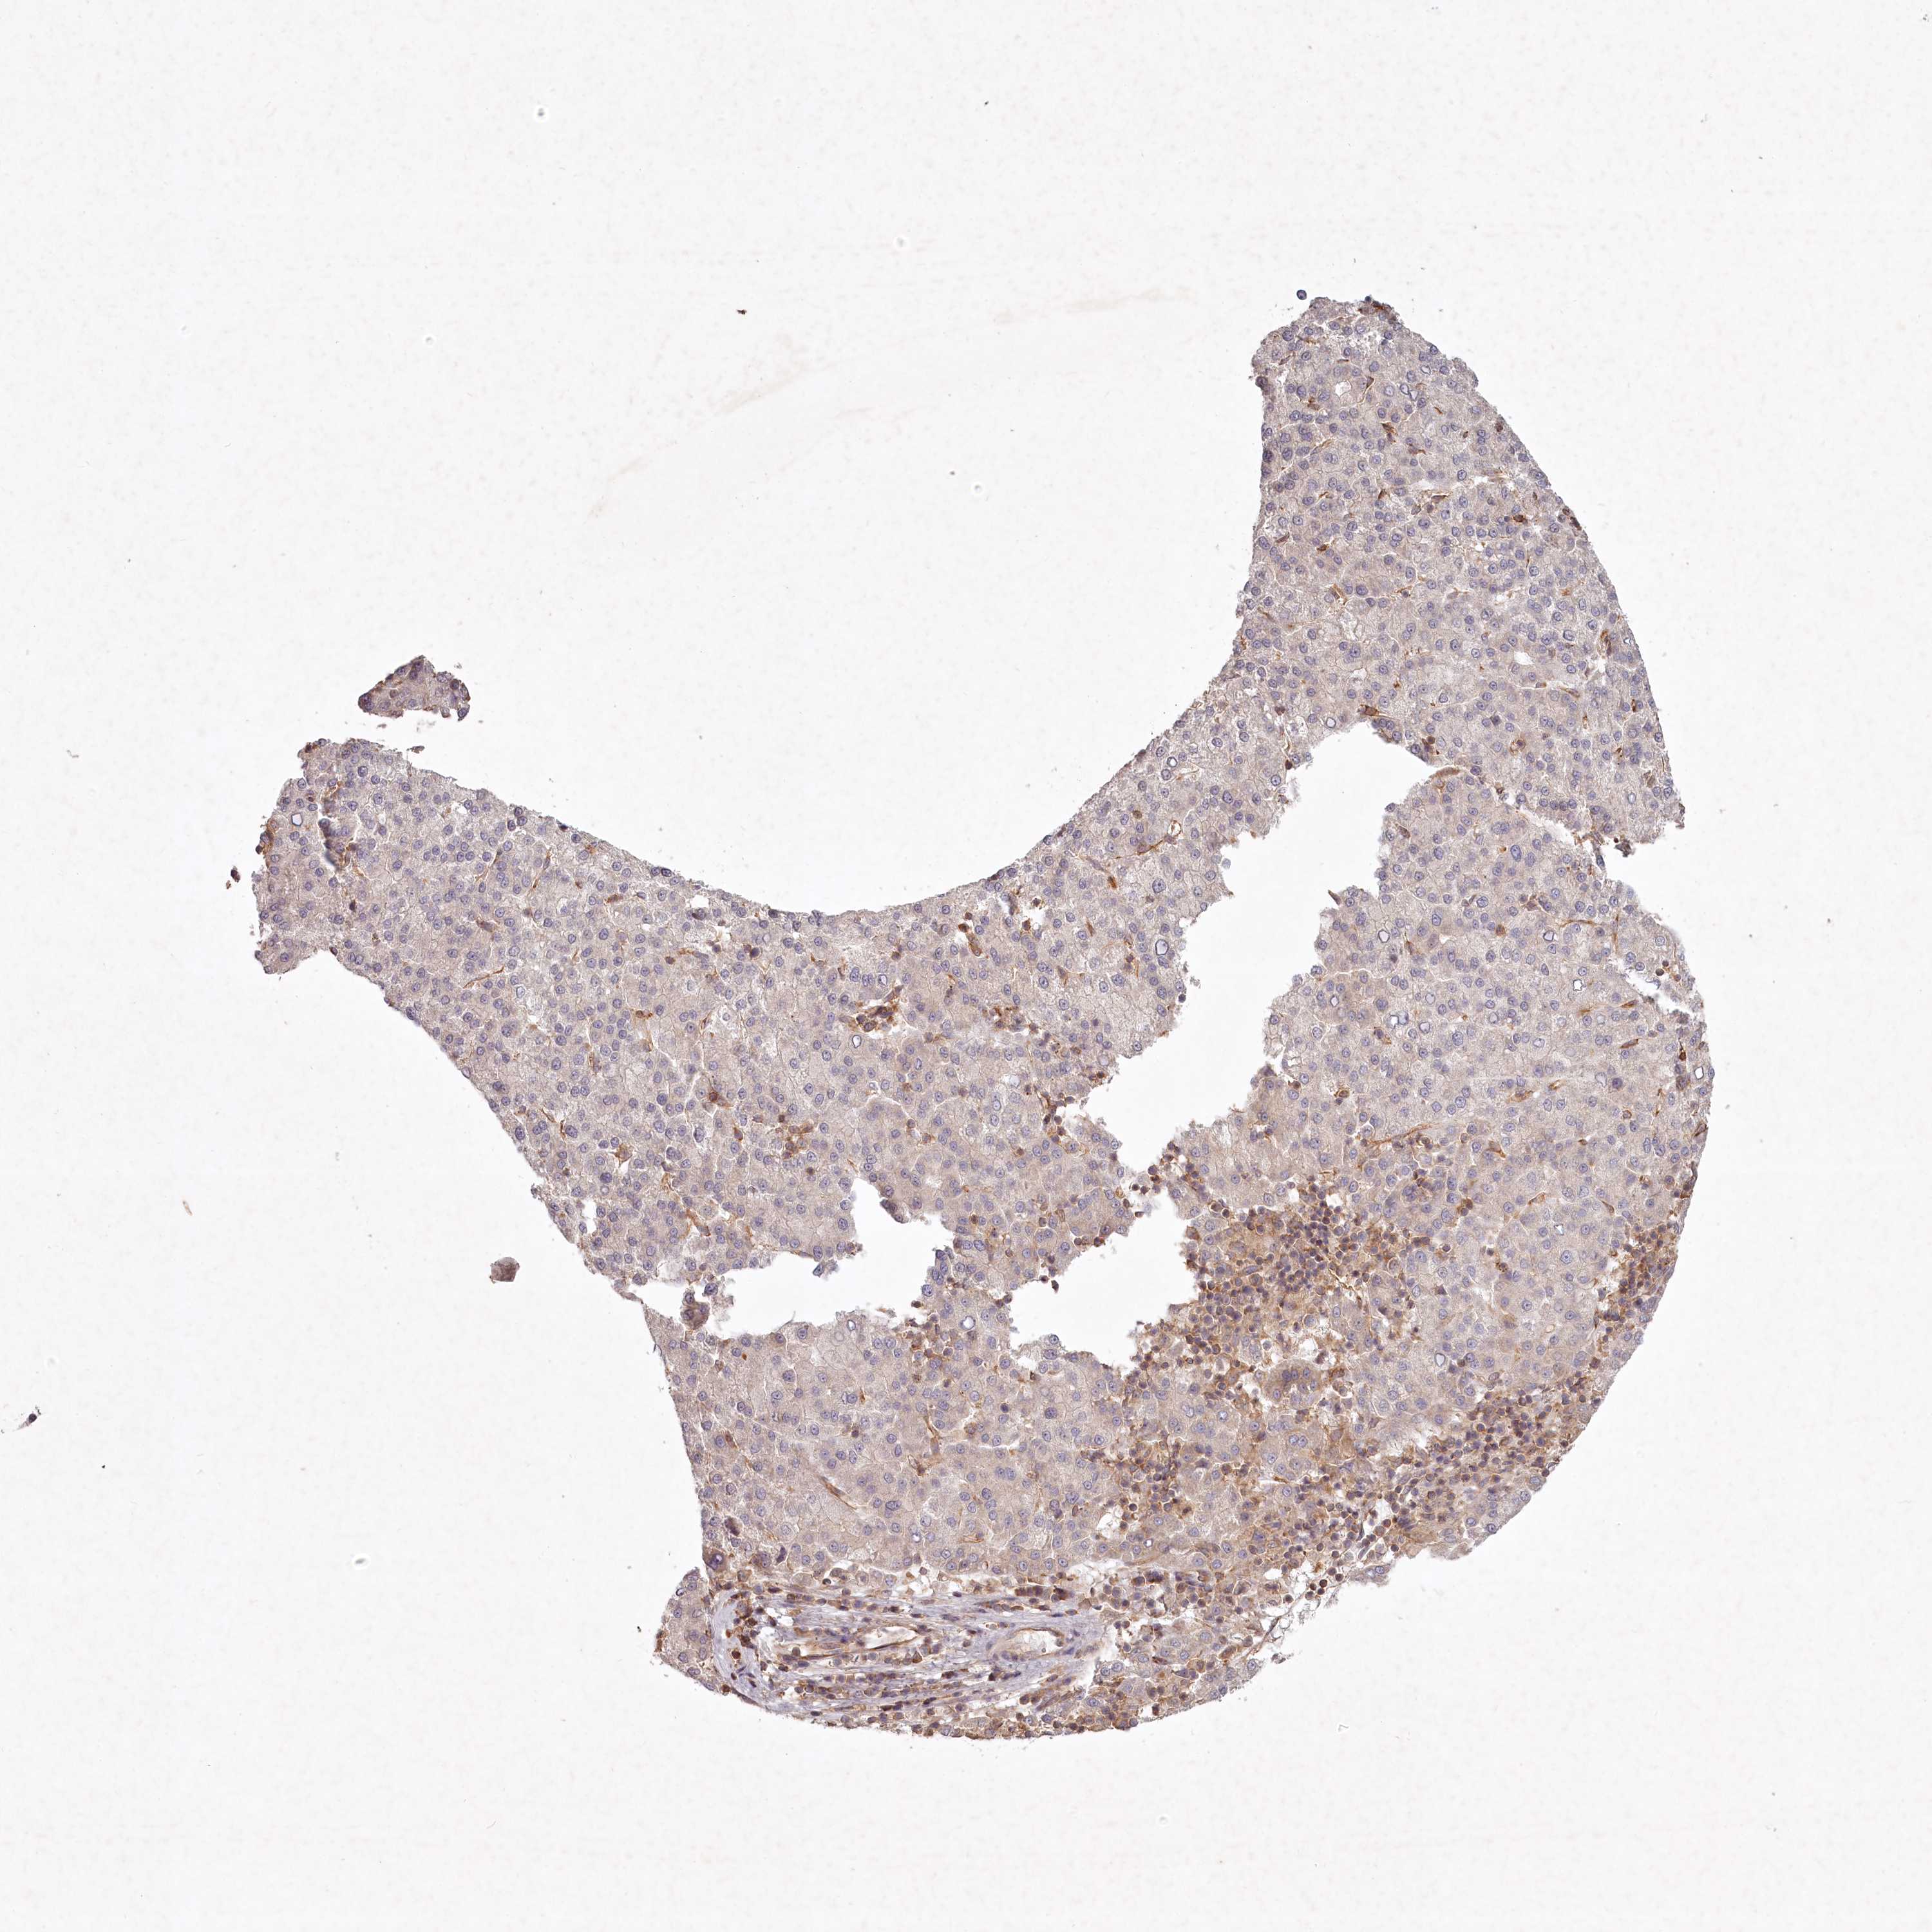

LIVER CANCER - Protein expressioni

A mouse-over function shows sample information and annotation data. Click on an image to view it in a full screen mode. Samples can be filtered based on level of antibody staining by selecting one or several of the following categories: high, medium, low and not detected. The assay and annotation is described here.

Note that samples used for immunohistochemistry by the Human Protein Atlas do not correspond to samples in the TCGA dataset.

Antibody stainingi

Antibody staining in the annotated cell types in the current human tissue is reported as not detected, low, medium, or high, based on conventional immunohistochemistry profiling in selected tissues. This score is based on the combination of the staining intensity and fraction of stained cells.

Each image is clickable and will lead to virtual microscopy that enables deeper exploration of all samples and also displays staining intensity scores, fraction scores and subcellular localization as well as patient and tissue information for each sample.

Antibody HPA038298

Staining

High

Medium

Low

Not detected

Intensity

Strong

Moderate

Weak

Negative

Quantity

>75%

75%-25%

<25%

None

Location

Nuclear

Cytoplasmic/membranous

Cytoplasmic/membranous,nuclear

Cholangiocarcinoma

Carcinoma, Hepatocellular, NOS